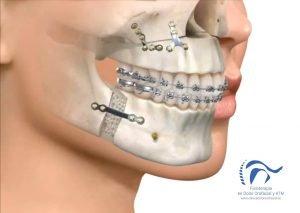

1. Los objetivos de la fisioterapia en cirugía maxilofacial.

Los objetivos de la fisioterapia en el paciente operado de cirugía maxilofacial, serán restablecer la función oral y mandibular al máximo, encontrándose como objetivos claros de la función la deglución, la fonación y la respiración.

Objetivos entre los que se encuentran disminuir la inflamación, aumentar la sensibilidad y restablecer el movimiento de la mandíbula.

3. Posibles complicaciones de la cirugía.

Dentro de las complicaciones más frecuentes están las mordidas abiertas que se pueden producir, es decir, que se genere un hueco que no permita contactar los dientes incisivos anteriores. Cuando esto se produce en las primeras horas posteriores a la cirugía, requiere en muchas ocasiones la reintervención casi inmediata para restablecer el buen alineamiento de los segmentos óseos. Si la mordida abierta anterior se produce durante los siguientes meses, es necesario evaluar de manera objetiva la ATM, para descarta una reabsorción condilar que pudiese estar ocasionando esto.

La hipoestesia o perdida de la sensibilidad es una consecuencia directa de la cirugía difícilmente evitable por la manera es que se produce el alargamiento o acortamiento del segmento mandibular. Es importante comenzar desde el inicio con la pautas encaminadas al restablecimiento de la sensibilidad. Pero en ocasiones se pueden dañar algunos nervios que se sitúan cerca de la zona afectada por la cirugía por lo que es importante evaluar la evolución de la sensibilidad con el fin de descartar la lesion nerviosa irreversible.

Algún vaso dañado podría ser una complicación inmediata de la cirugía, que se repara de manera inmediata en la cirugía y que pone de manifiesto la importancia de la comunicación entre los distintos equipos, cirugía y fisioterapia, para poder conocer de primera mano cualquier suceso de importancia para establecer un correcto programa de recuperación que no dañe ni ponga en peligro ningún aspecto de la cirugía.

En ocasiones también se producen fracturas óseas indeseadas en la cirugía que necesitan ser restablecidas de inmediato.